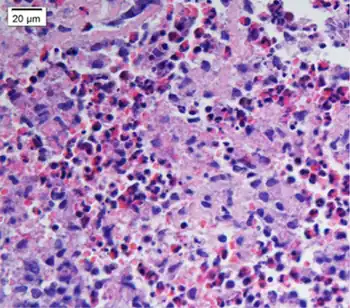

| Biopsy shows remarkable eosinophilic cell infiltration at interstitium of myocardium and necrosis of myocardium | |

In eosinophilic myocarditis, echocardiography typically gives non-specific and only occasional findings of endocardium thickening, left ventricular hypertrophy, left ventricle dilation, and involvement of the mitral and/or tricuspid valves. However, in acute necrotizing eosinophilic myocarditis, echocardiography usually gives diagnostically helpful evidence of a non-enlarged heart with a thickened and poorly contracting left ventricle. Gadolinium-based cardiac magnetic resonance imaging is the most useful non-invasive procedure for diagnosing eosinophilic myocarditis. It supports this diagnosis if it shows at least two of the following abnormalities: a) an increased signal in T2-weighted images; b) an increased global myocardial early enhancement ratio between myocardial and skeletal muscle in enhanced T1 images and c) one or more focal enhancements distributed in a non-vascular pattern in late enhanced T1-weighted images. Additionally, and unlike in other forms of myocarditis, eosinophilic myocarditis may also show enhanced gadolinium uptake in the sub-endocardium.[1][7] However, the only definitive test for eosinophilic myocarditis is cardiac muscle biopsy showing the presence of eosinophilic infiltration. Since the disorder may be patchy, multiple tissue samples taken during the procedure improve the chances of uncovering the pathology but in any case, negative results do not exclude the diagnosis.[5][7]